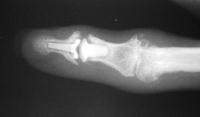

The final implant:

Xrays one year out.